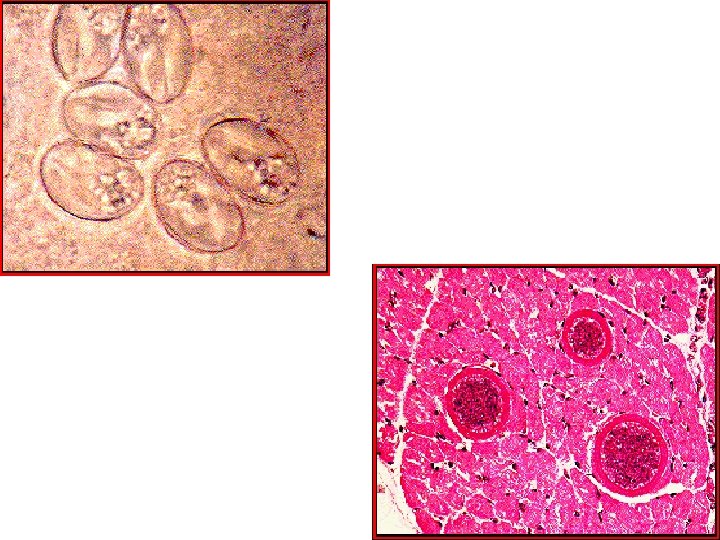

Genus Sarcocystis Morphology: =Oocyst broadly oval lying along infected muscle fibers, hyaline appearance and enclose in a membrane = contains 2 large sporocyst inside tubular mass (Meischer tube) filled up with 4 mature cresent-shaped sporozoites = sporocyst/rainy corpuscles/trophozoite are banana-shape with subspherical nucleus found in the muscle thread extending from end to end

Lab. Diag. : 1. Demonstration of oocyst in feces / duodenal aspirate 2. Biopsy of tissue of small intestine or colon demonstrate Meischer tube Treatment: = None for tissue infection (Supportive – self-limiting) = For intestinal infection: Trimethoprim + Sulfamethoxazole Pyrimethamine + Sulfadiazine (alternate drug) Prevention: = Avoid contact with infected animal host = Adequate cooking of all meat